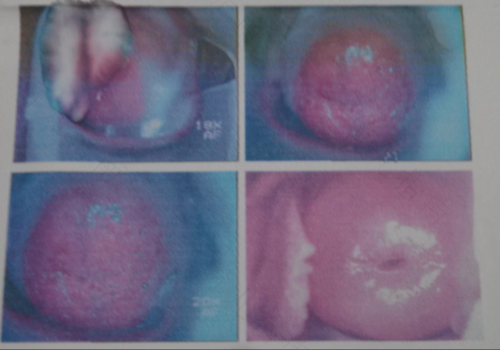

宫颈糜烂是一种常见的妇科疾病,多在育龄女性身上发生,这是慢性宫颈炎症的一种,由于宫颈颜色发红,从外观上看,就像皮肤湿疹样的糜烂,那么,宫颈糜烂深一度严重吗?

宫颈糜烂深一度,不算严重程度,是属于轻度炎症,宫颈糜烂按照糜烂面积和病情程度,可分为轻度、中度和重度这三个层次,而宫颈糜烂一度是属于比较轻度的。但是对于宫颈糜烂一度,也要多注意观察和护理,避免糜烂程度加重。